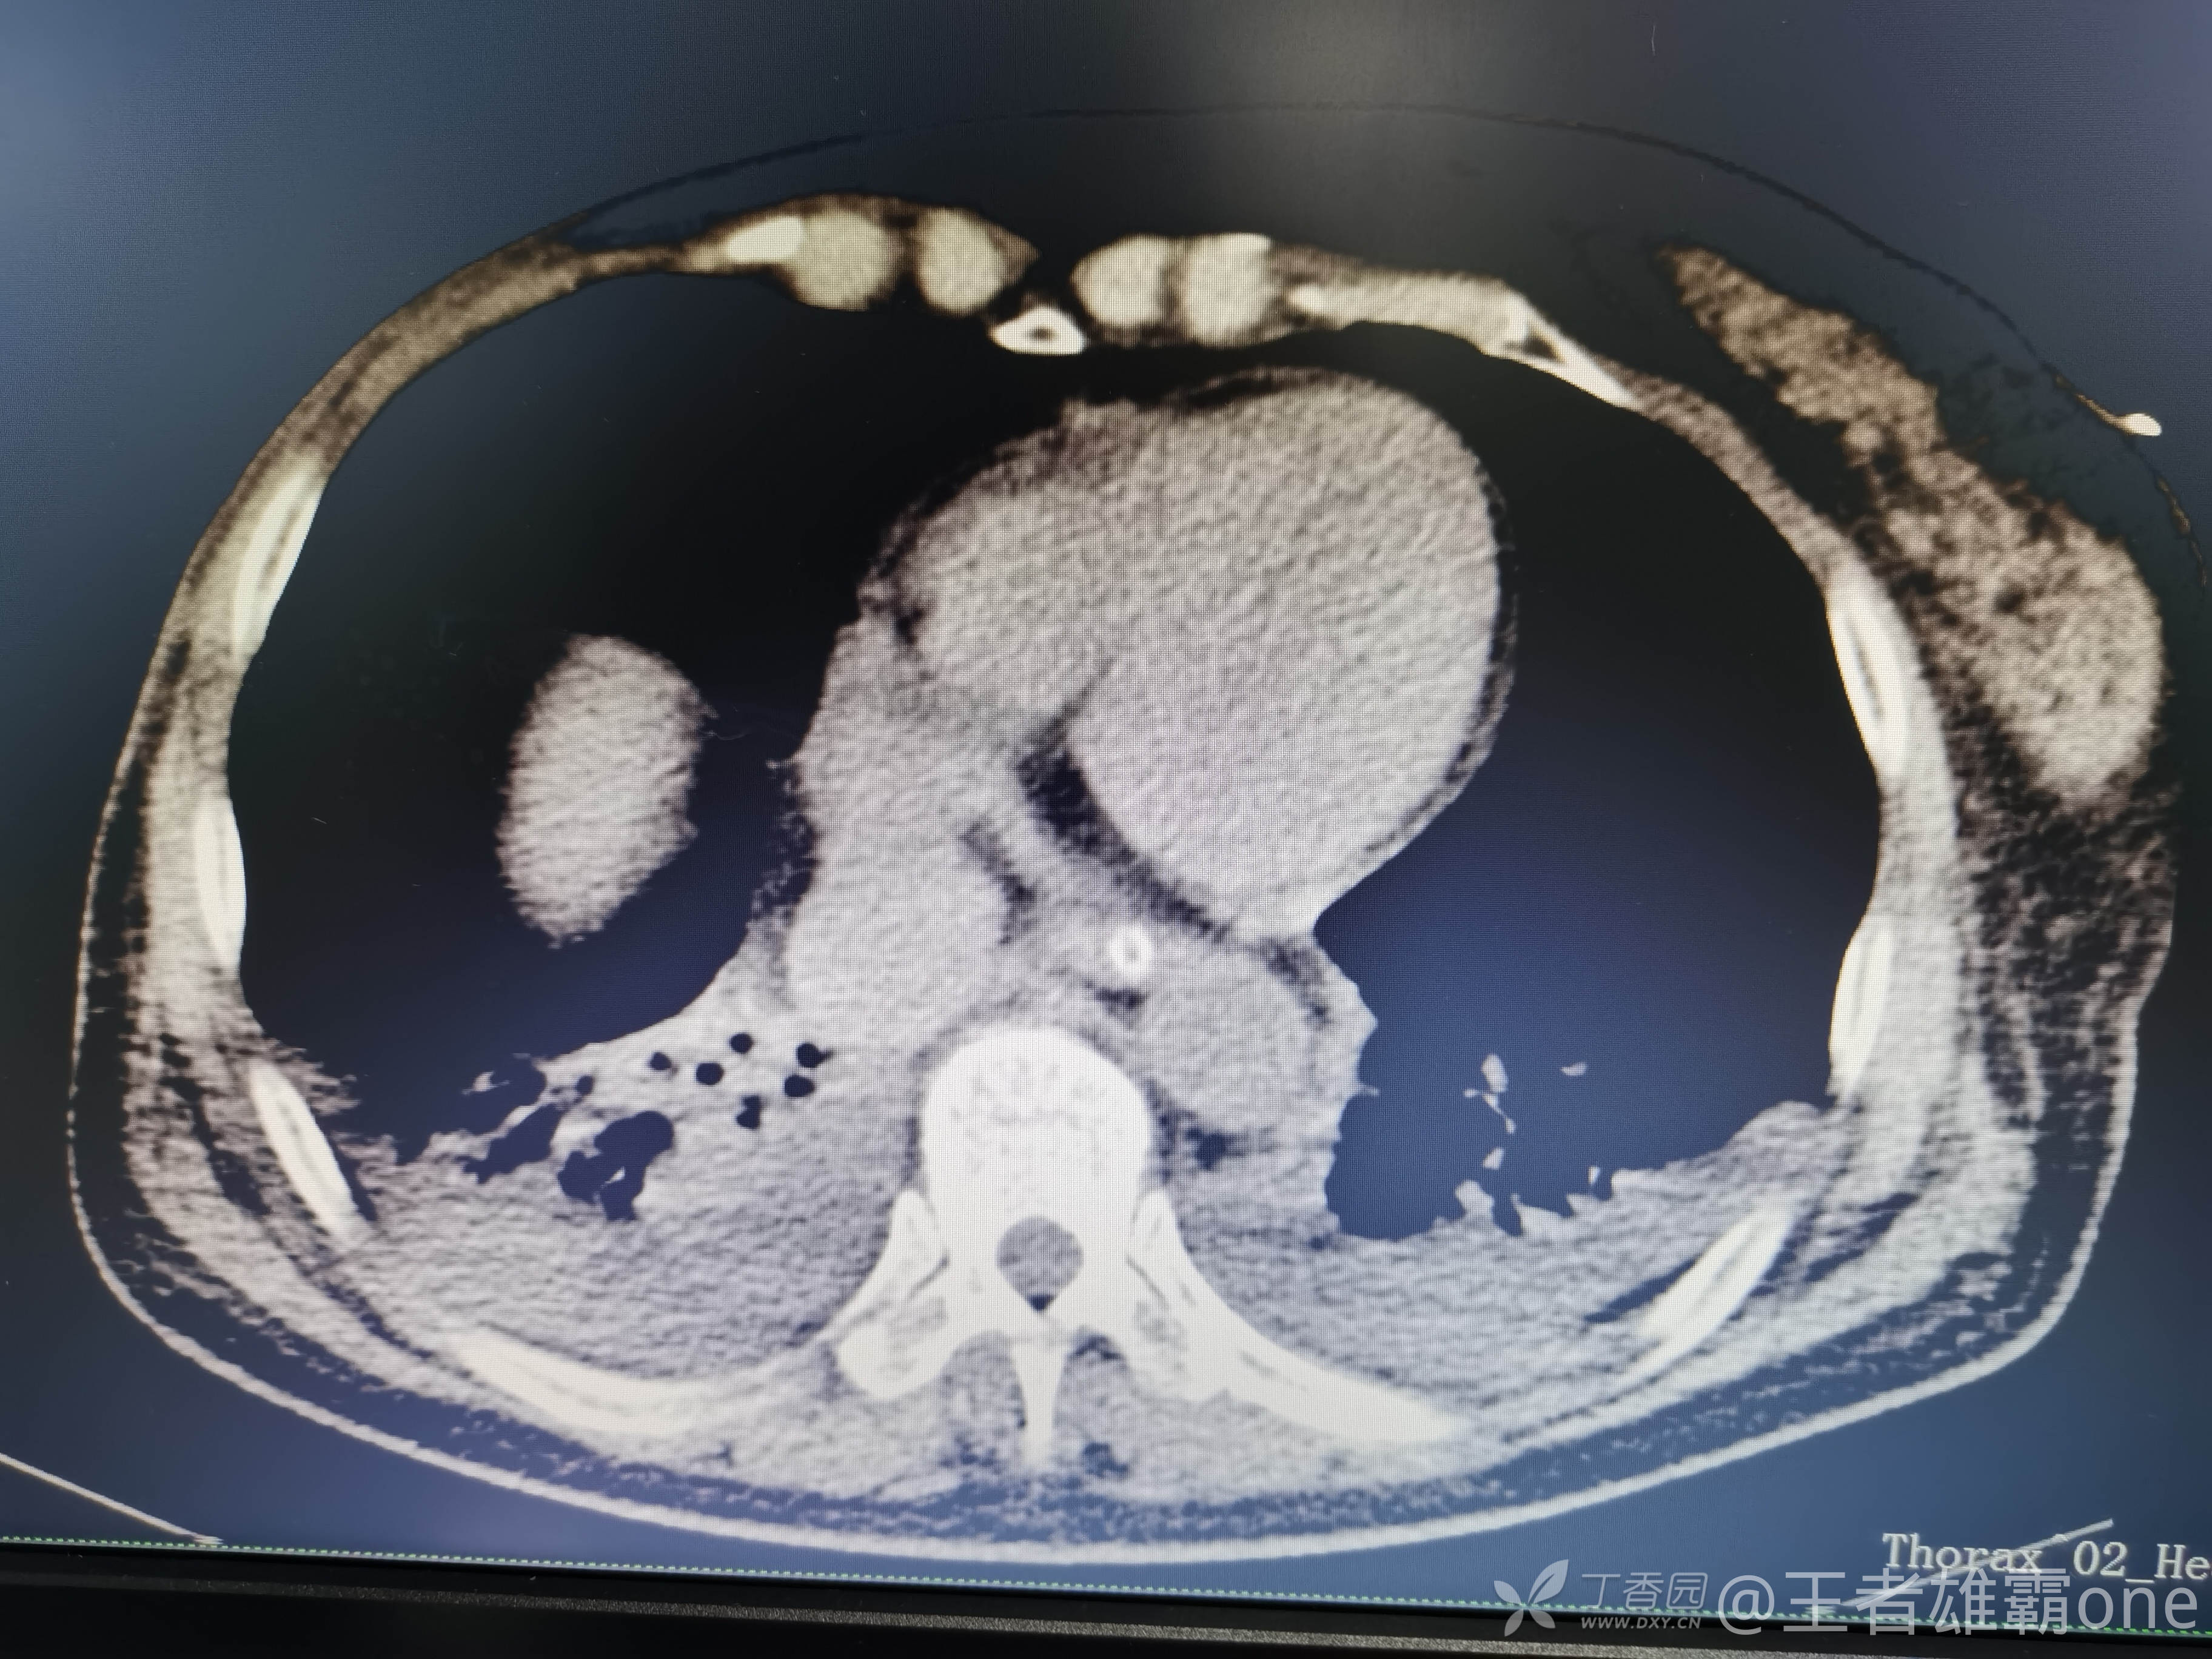

早上复查血常规:血红蛋白100g/L,白细胞11.1×109/L,血小板29×109/L。凝血功能:APTT37.9s,纤维蛋白原3.01g/L,凝血酶时间18.6s,D二聚体21530ug/L。生化:白蛋白36.2g/L,胆红素指标正常,谷丙56U/L,总胆红素38mmol/L,直接胆红素12.1mmol/L,谷草57U/L,肌酐91.1ummol/L,尿素13.97mmol/L,超敏C反应蛋白142.1mg/L。降钙素原17.70ng/ml。脑钠肽前体2164pg/ml。复查胸部CT:

那么问题来了,出现呼吸衰竭气管插管的病因是?请大家讨论分析!